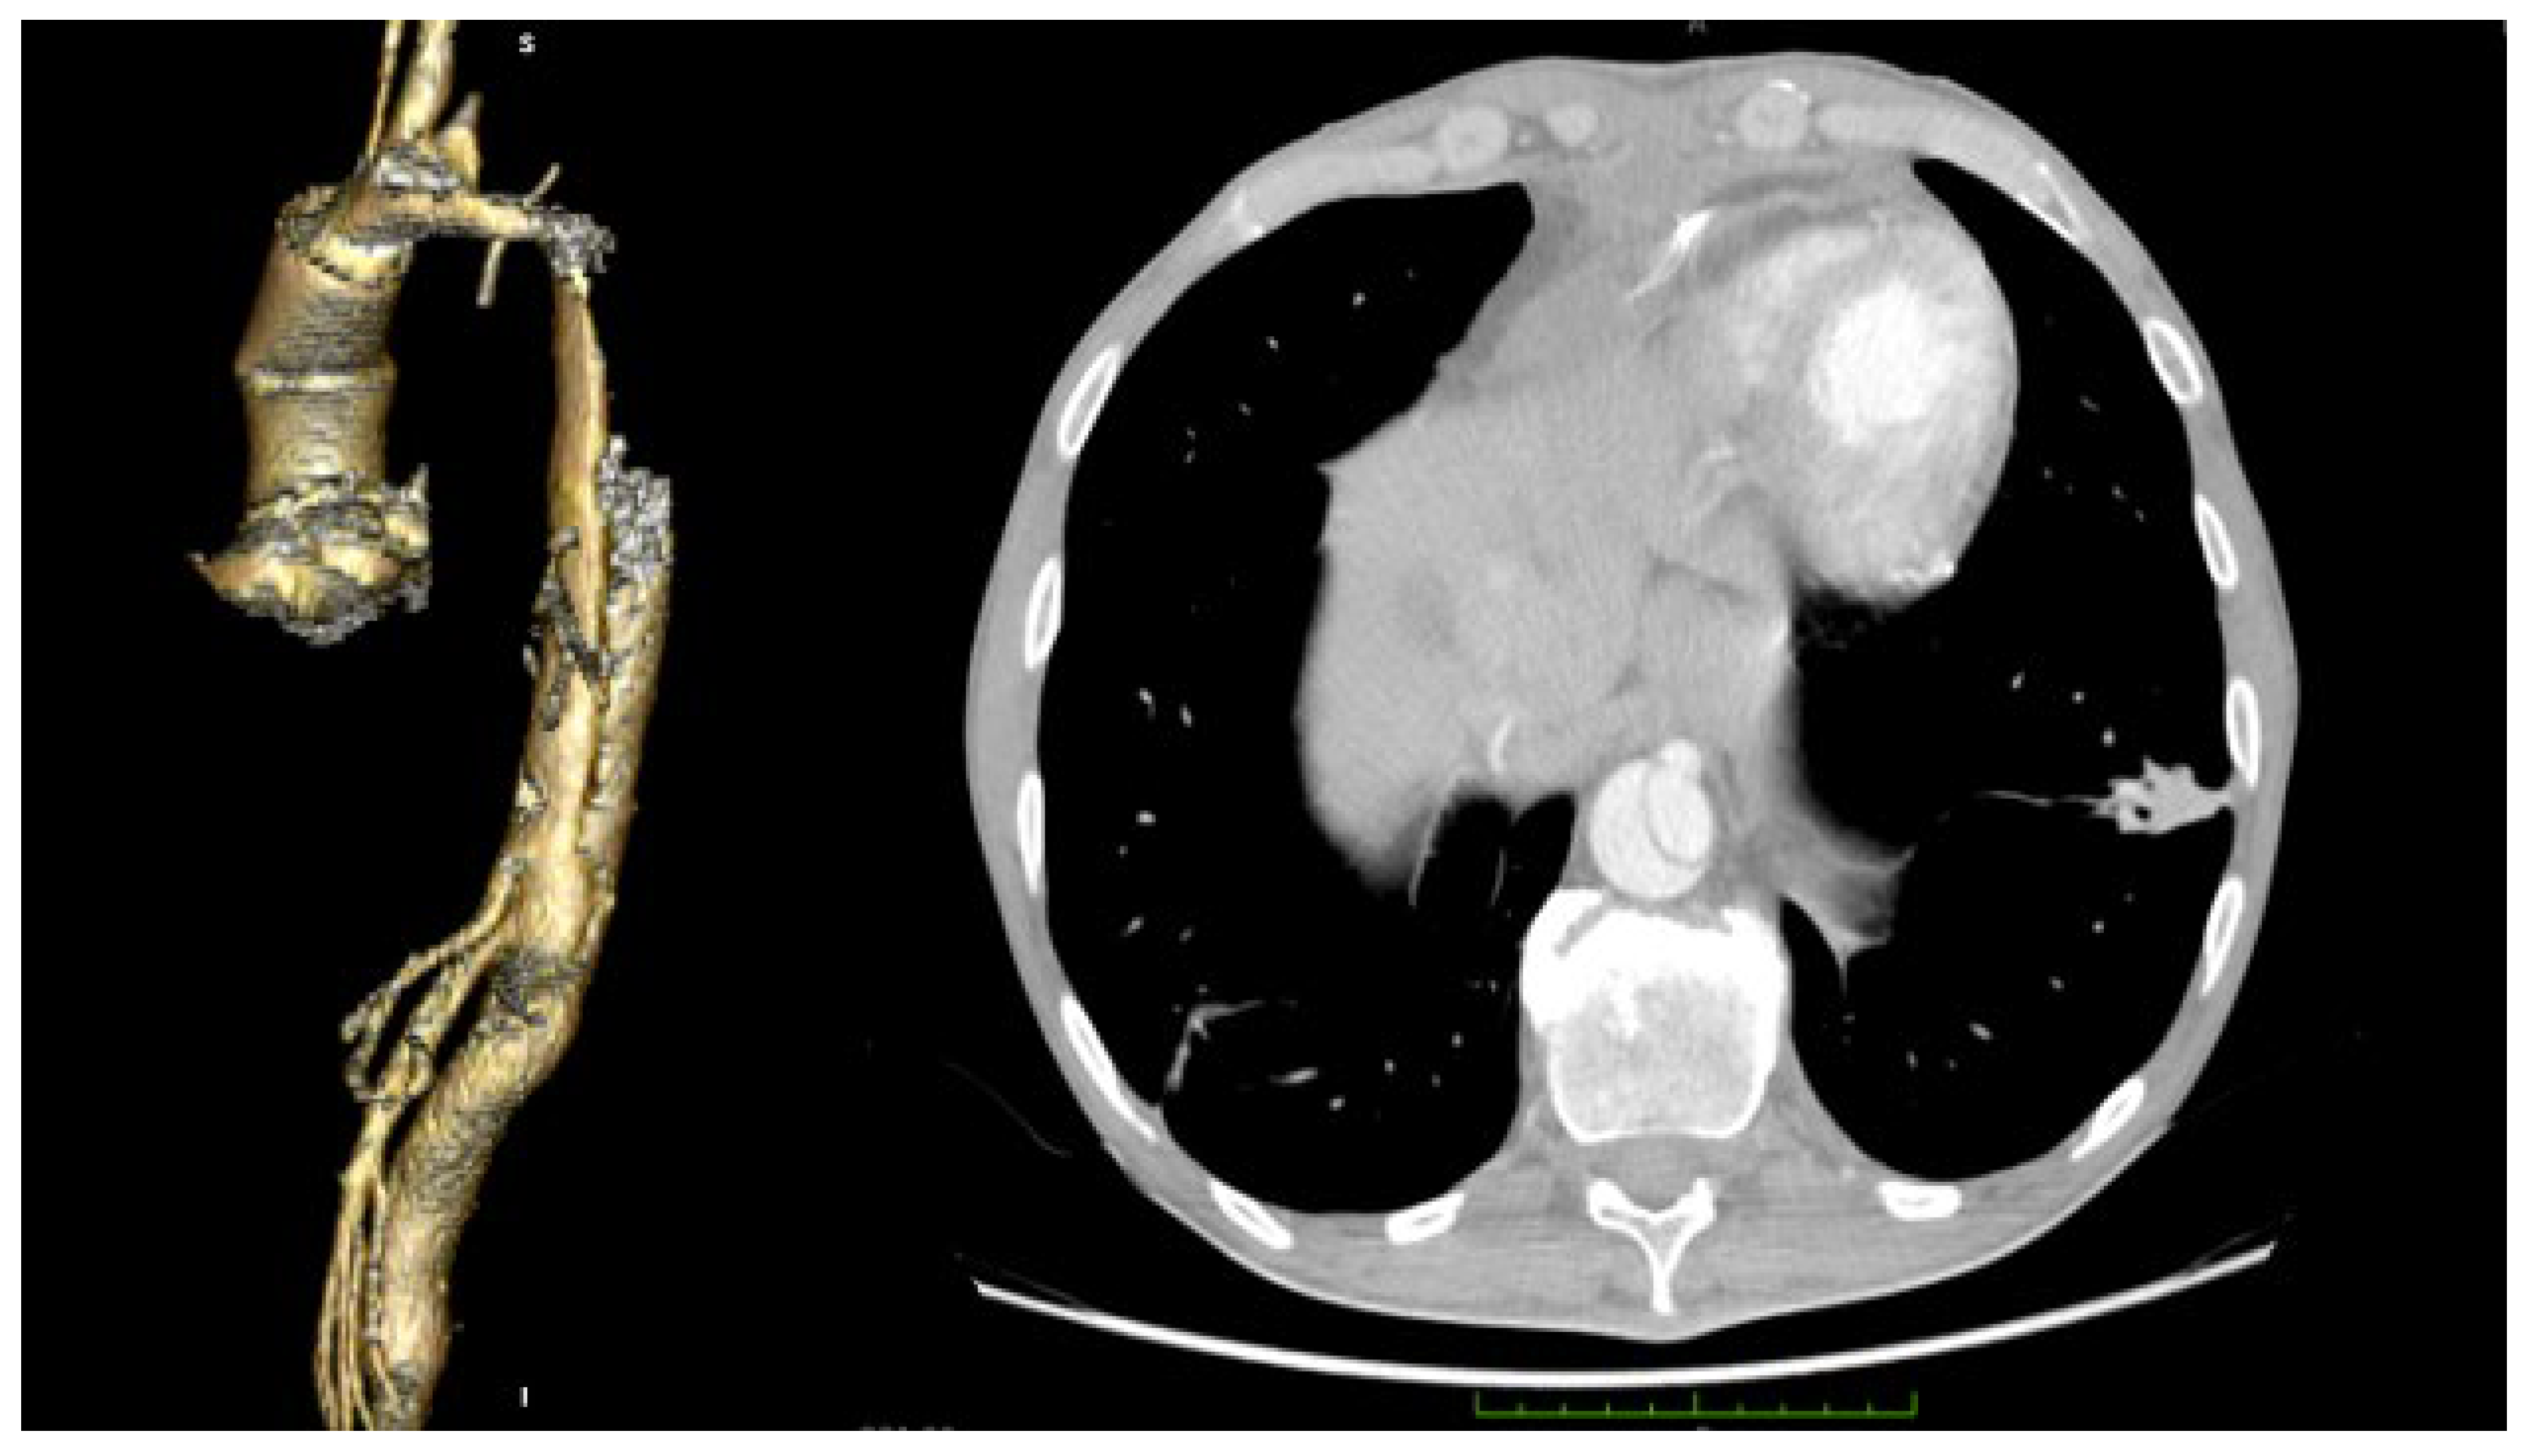

2. Case Report